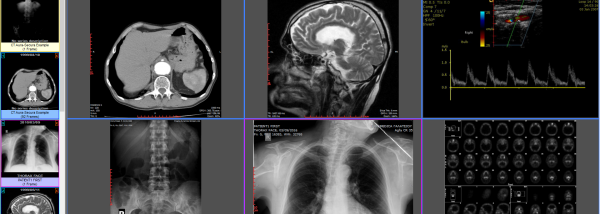

Digimizer

... professionals and enthusiasts who require precise and accurate image analysis. Digimizer allows users to import a wide range ... easy for beginners to navigate. It also offers advanced features for the more experienced users, such as calibration, ...